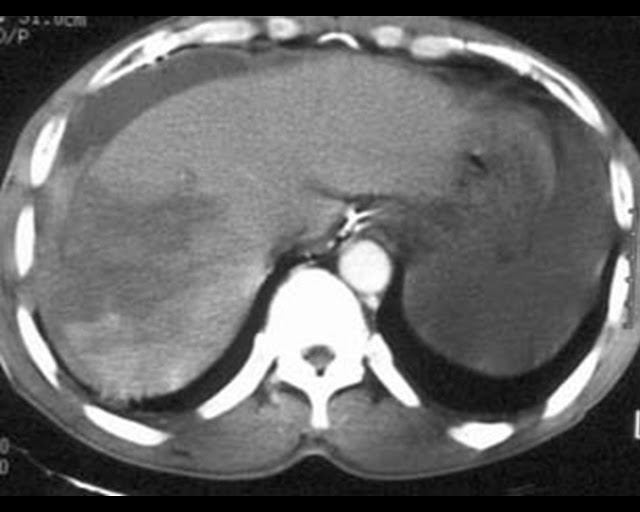

There is simply so much “going on” in this image that the audience will be unable to derive meaning from any of the images (or worse still from the speech) because they are trying to decide which image to actually look at. Help the audience and simply project each image as required. (It’s a Grade IV Liver laceration)